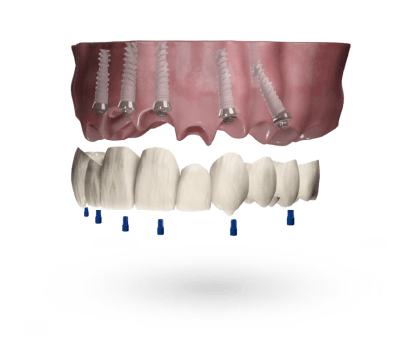

Wybierz rodzaj uzupełnienia

Wybierz platformę